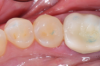

Polishing was the finishing step. Given the anatomy and smoothed-out surface, a small brush sufficed. Posteriors do not necessarily call for the same amount of polishing as an anterior restoration, but polishing is nevertheless a good step to take at the end. Figure 3 shows the final result of the restoration. It was a highly esthetic match.